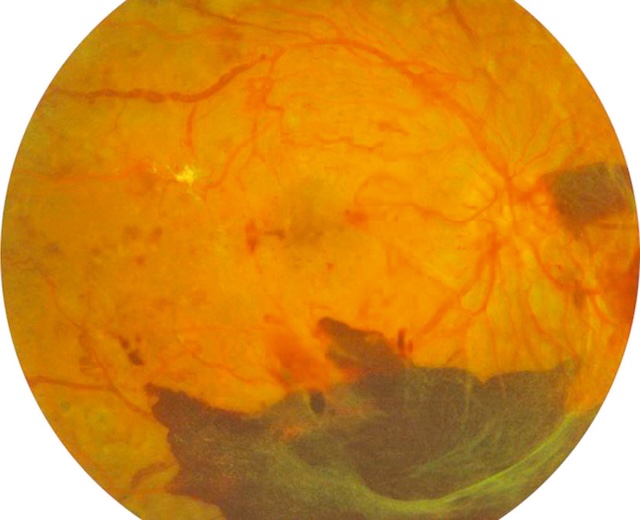

- – des hémorragies prérétiniennes ou intravitréennes surviennent à partir des néovaisseaux (fig. 20.9).

Fig. 20.9 Rétinopathie diabétique proliférante avec hémorragies prérétiniennes. L’image montre un fond d’œil typique d’une rétinopathie diabétique proliférante compliquée. Dans la partie inférieure, une large hémorragie prérétinienne s’étale en nappe, d’aspect sombre et dense, masquant partiellement les structures vasculaires sous-jacentes. On distingue en périphérie de fines tractions fibrovasculaires blanchâtres, traduisant l’organisation de néovaisseaux anciens. Les vaisseaux rétiniens sont tortueux, parfois dilatés, avec un fond d’œil diffusément altéré. Un discret œdème maculaire est aussi visible plus en arrière-plan. Ce tableau traduit une forme avancée de la pathologie, à risque élevé de complications comme un décollement tractionnel de la rétine.

Des complications peuvent survenir :

- • décollement de la rétine dû à la traction exercée sur la rétine par le tissu fibreux de soutien des néovaisseaux (prolifération fibrovasculaire) : on parle de décollement de rétine par traction (fig. 20.10) par opposition au décollement de rétine rhegmatogène induit primitivement par une déchirure de la rétine;

Fig. 20.10 A. Retinopathie diabétique proliférante avec fibrose prérétinienne (flèche bleue). B. Décollement de rétine tractionnel (flèche rouges), bien visible en OCT. Sur l’image A, un fond d’œil révèle une rétinopathie diabétique proliférante marquée par une fibrose prérétinienne épaisse et blanchâtre s’étendant en arc autour de la papille et de la macula. La traction générée par ces membranes fibrovasculaires est évidente, avec des plis rétiniens radiaires et un soulèvement localisé de la rétine. L’image B, en OCT, confirme un décollement de rétine de type tractionnel : la rétine est soulevée sans espace sous-rétinien liquidien net, et les insertions des tractions sont visibles de part et d’autre, souvent à proximité des néovaisseaux. L’ensemble témoigne d’un stade avancé de complication diabétique nécessitant une prise en charge chirurgicale.